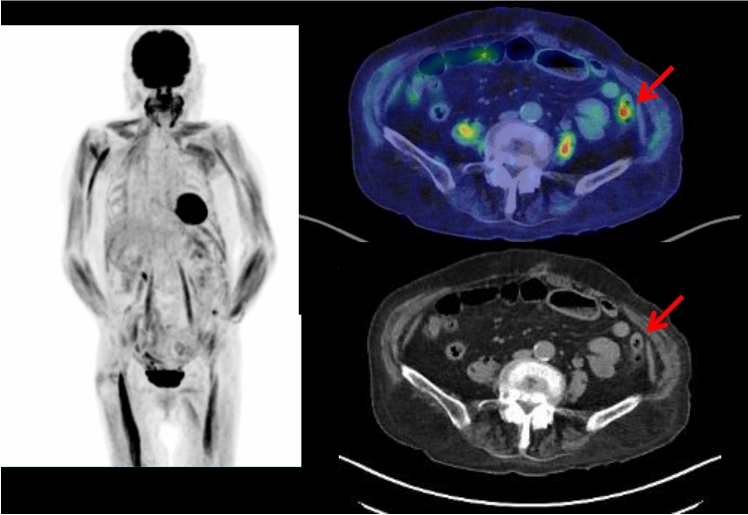

To date, the cases of FDG-avid myelodysplastic syndrome and non-Hodgkin T cell lymphoma on FDG PET/CT in patients with SS have been reported [31, 32]. In the reported patient of myelodysplastic syndrome, FDG PET/CT showed multiple cutaneous foci with increased FDG uptake throughout the body, which were some of the cutaneous erythematous nodules of SS [31]. FDG PET/CT also showed multiple FDG-avid lymph nodes in the mediastinum, bilateral pulmonary hili and abdomen, and diffusively increased FDG uptake of bone marrow. In the reported case of T cell lymphoma, FDG PET/CT showed hepatomegaly with intense FDG uptake, which was diagnosed as T cell lymphoma by a liver biopsy [32]. Our case of SS showed FDG-avid follicular lymphoma lesions and gastric cancer (Fig. 2).

Fig. 2.

In a 76-year-old male with Sweet syndrome, whole-body FDG PET maximum projection and cross-sectional images showed FDG-avid (SUVmax 2.1) lymphadenopathy in the both axillary and hilar regions and in the both external iliac and left inguinal regions (arrows). The biopsy of the left inguinal lymph node revealed follicular lymphoma. In addition, focal intensive FDG uptake (SUVmax 5.0) was also seen in the lower part of gastric corpus (arrowhead), which was later diagnosed as gastric cancer by endoscopic biopsy